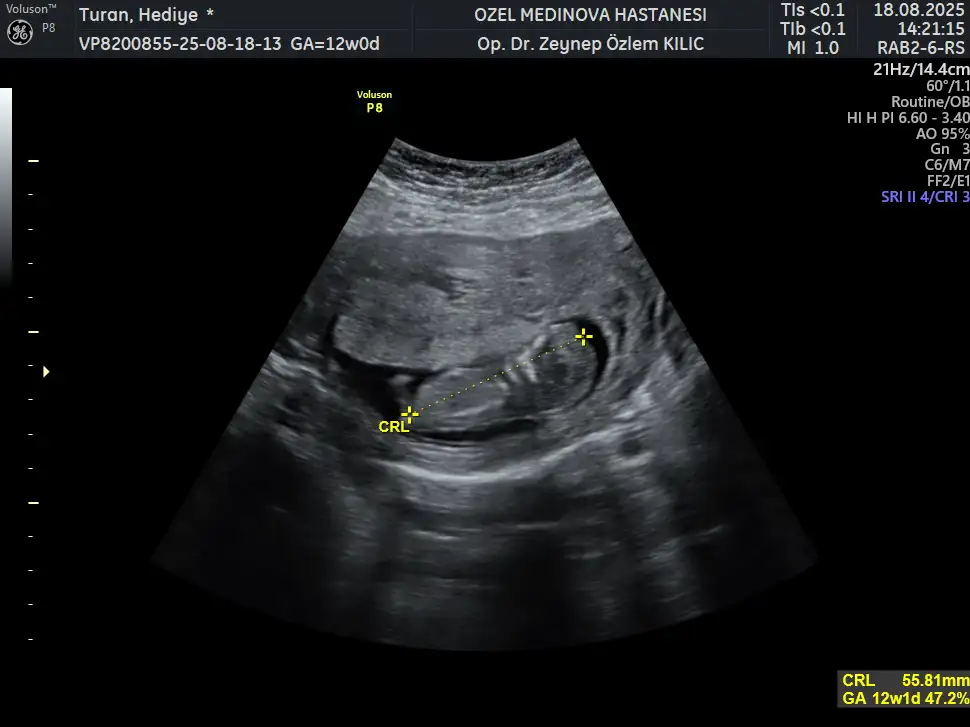

13+4 tahminde bulunabilir misiniz şimdiden teşekkür ederim.